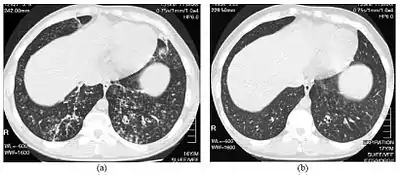

| High-resolution computed tomography images of the lower chest in a 16-year-old boy with diffuse panbronchiolitis | |

The diagnosis of DPB requires analysis of the lungs and bronchiolar tissues, which can require a lung biopsy, or the more preferred high resolution computed tomography (HRCT) scan of the lungs.[7] The diagnostic criteria include severe inflammation in all layers of the respiratory bronchioles and lung tissue lesions that appear as nodules within the terminal and respiratory bronchioles in both lungs.[4] The nodules in DPB appear as opaque lumps when viewed on X-rays of the lung, and can cause airway obstruction, which is evaluated by a pulmonary function test, or PFT.[6] Lung X-rays can also reveal dilation of the bronchiolar passages, another sign of DBP. HRCT scans often show blockages of some bronchiolar passages with mucus, which is referred to as the "tree-in-bud" pattern.[7] Hypoxemia, another sign of breathing difficulty, is revealed by measuring the oxygen and carbon dioxide content of the blood, using a blood test called arterial blood gas. Other findings observed with DPB include the proliferation of lymphocytes (white blood cells that fight infection), neutrophils, and foamy histiocytes (tissue macrophages) in the lung lining. Bacteria such as H. influenzae and P. aeruginosa are also detectable, with the latter becoming more prominent as the disease progresses.[4][5] The white blood, bacterial and other cellular content of the blood can be measured by taking a complete blood count (CBC). Elevated levels of IgG and IgA (classes of immunoglobulins) may be seen, as well as the presence of rheumatoid factor (an indicator of autoimmunity). Hemagglutination, a clumping of red blood cells in response to the presence of antibodies in the blood, may also occur. Neutrophils, beta-defensins, leukotrienes, and chemokines can also be detected in bronchoalveolar lavage fluid injected then removed from the bronchiolar airways of individuals with DPB, for evaluation.[4][9]